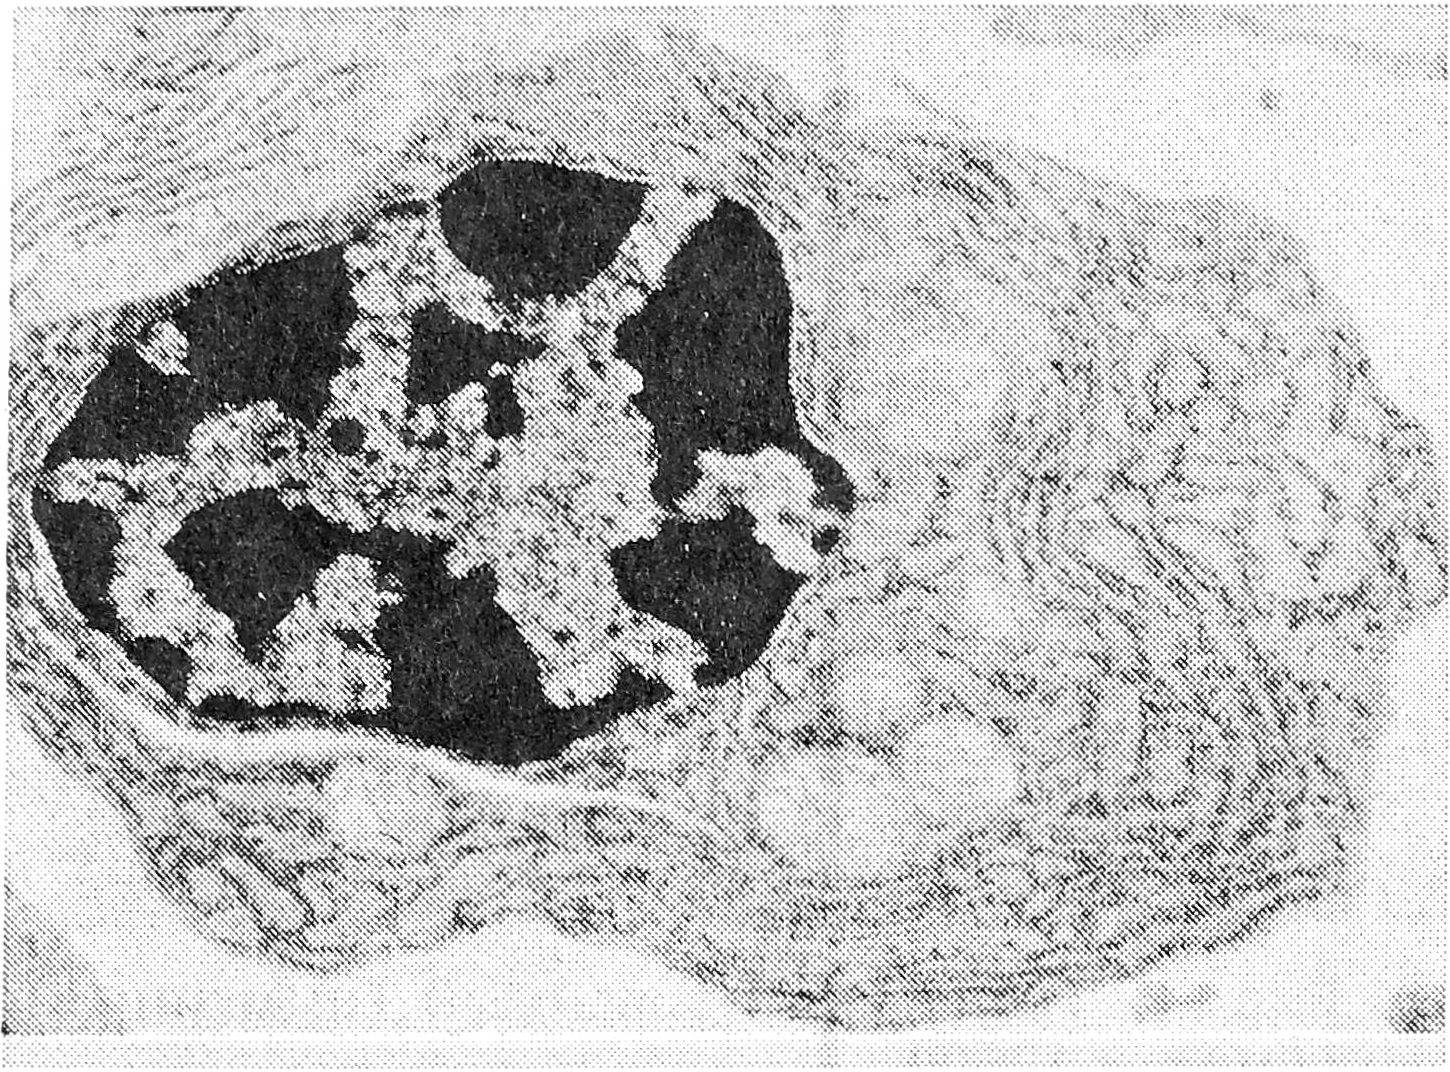

При исследовании под электронным микроскопом было видно, что стенки синусов выстланы литориальными (береговыми) клетками, которые являются продолжением эндотелия лимфатических сосудов. Ультраструктура этих клеток подробно описана [5]. Основные элементы синусов — ретикулярные клетки — имеют размеры от 10 до 25 мкм, овальное ядро с преимущественно диспергированным хроматином и один или два ядрышка. Цитолазма образует выросты и длинные отростки, при помощи которых ретикулярные клетки соединяются друг с другом (десмосомы) и контактируют с лимфоцитами. Из органелл обнаруживаются немногочисленные митохондрии, свободные рибосомы и лизосомы (рис. 1). Ретикулярные клетки являются фиксированными макрофагами [12] и делятся на две функциональные группы — фагоцитирующие и нефагоцитирующие [5], причем в норме, по нашим наблюдениям, преобладают последние. Кроме того, в синусах есть и свободные макрофаги — пришлые клетки моноцитарного происхождения. Их ультраструктура идентична другим интерстициальным макрофагам [12]. Качество таких клеток в норме незначительно. Содержащиеся в синусах лимфоциты представлены в основном так называемыми нетрансформированными формами от 5 до 11 мкм с узким ободком цитоплазмы, единичными и небольшими выростами, округлым ядром без выраженных инвагинаций с преобладанием плотного хроматина и одним ядрышком. Органеллы цитоплазмы незначительны и представлены несколькими митохондриями, свободными рибосомами и единичными лизосомами (рис. 2). Содержание других клеточных элементов в норме в синусах невелико — их характеристика будет приведена ниже при описании опухолевого процесса.

Рис. 1. Ретикулярная клетка, х 10000.